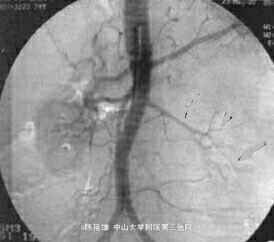

影像学表现:CT平扫,左肾区巨大、不规则形包块,其后内见片状低密度坏死灶,右内近边缘处另见2枚高密度影,肿块最大层面直径约13.2 cm×12.2 cm,周围结构受压移位,部分结构与肿块界限欠清。DSA提示:相当于左肾位置似见左肾动脉、左肾轮廓及其动脉的正常分支,未见明显肿瘤血管,腹主动脉其他部位未见明确动脉分支向“假肾影”供血。DSA诊断肾细胞癌证据小足,遂放弃介入治疗。左肾区肿块穿刺活检病理:小细胞性恶性肿瘤,考虑为恶性淋巴瘤,免疫组织化学染色CD20普遍阳性,支持B细胞淋巴瘤。行标准B细胞淋巴瘤化疗。